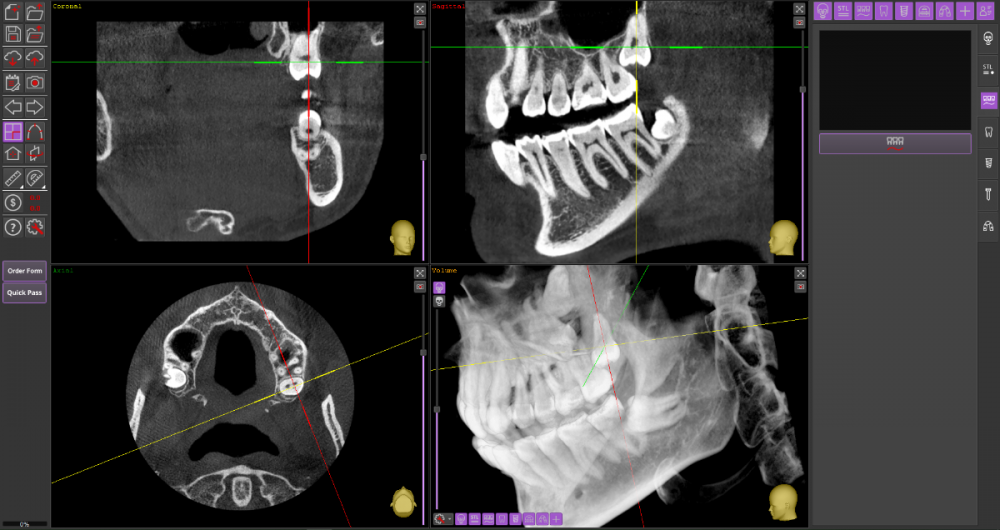

Прошу Вашего совета по поводу удаления восьмых зубов.

Из жалоб есть непродолжительная ноющая боль в правой нижней челюсти, не связанная с внешними раздражителями.

1. Необходимо ли удаление зубов мудрости?

2. Возможно ли удаление амбулаторно, без общего наркоза?

3. Нет ли риска для семёрок при удалении.

DICOM во вложении на Яндекс.Диске https://disk.yandex.ru/d/mBS1B4TYMHIf1A

Виновником боли в н.ч. справа может быть, например зуб 46, не только 48.

1. Удаление 8-х зубов скорее всего необходимо

2. Удаление амбулаторно вполне возможно. Общая анестезия (наркоз) совершенно необязательна, местной анестезии достаточно.

3. Несчастные случаи бывают, но крайне редко.